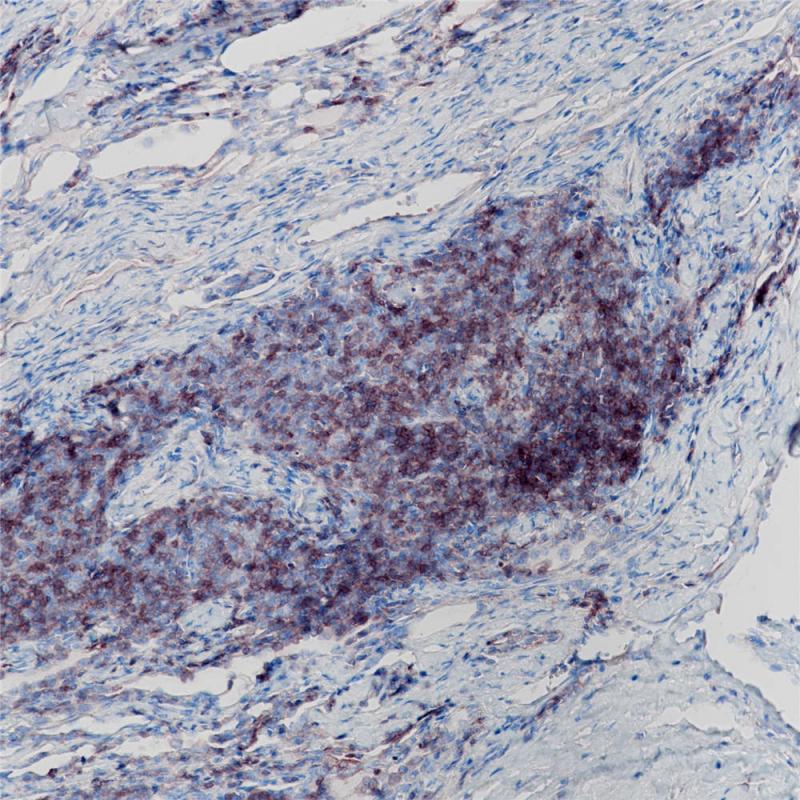

CD1a 重组兔单克隆抗体

阳性对照

胸腺瘤